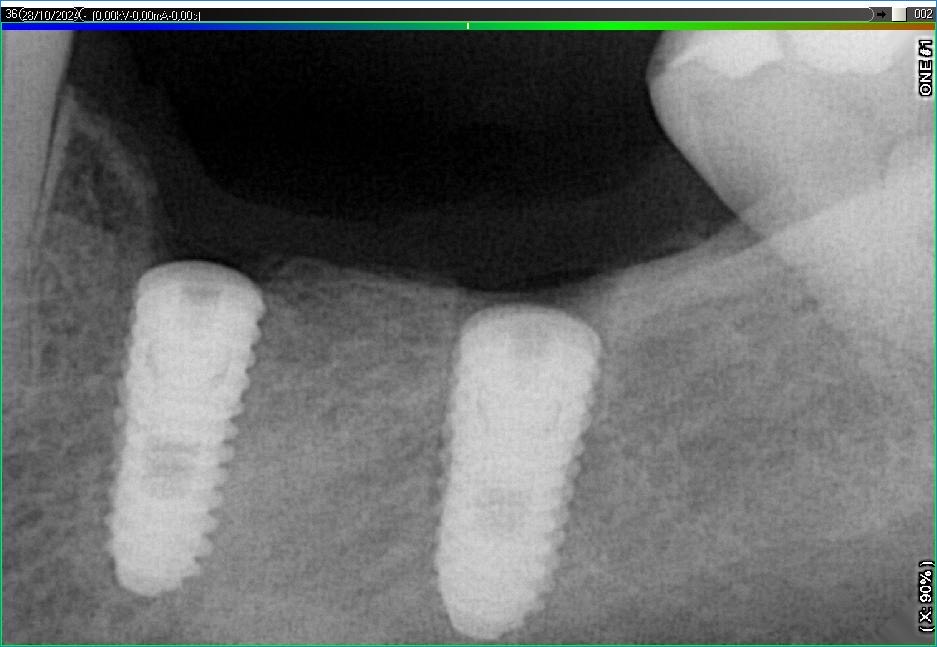

Імплантація